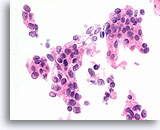

Atypische proliferatieve ductale laesie, Borst FNA, Diff-Quick gekleurde uitstrijk.

De ductale cellen zijn in drie dimensies opgestapeld. Er is geen duidelijke populatie myoepitheliale cellen en linksonder is er slechts focaal mogelijk gedeelde polariteit van aangrenzende ductale cellen.

Atypische proliferatieve ductale laesie, Borst FNA, Diff-Quick gekleurde uitstrijk.

De ductale cellen zijn in drie dimensies opgestapeld. Er is geen duidelijke populatie myoepitheliale cellen en linksonder is er slechts focaal mogelijk gedeelde polariteit van aangrenzende ductale cellen.